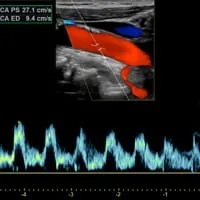

Ultrasound is performed without any radiation, and demonstrates blood flow in the veins in real time. This allows ultrasound evaluation during dynamic movement of the arms. At the same time, bones interfere with ultrasound and create blind spots. Thus, ultrasound may not directly demonstrate venous compression in the thoracic outlet. However, ultrasound shows blood clots quite well, as well as abnormal venous waveforms just beyond the blind spot. Ultrasound does not demonstrate fibrous bands and muscle anomalies in detail.